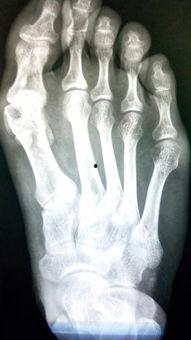

拆石膏其实是一门技术活。医生会先用小刀沿着石膏边缘轻轻划开,注意力度要适中,以免伤到皮肤。接着,他们会用专用的石膏剪,沿着划开的边缘将石膏剪开。这个过程需要耐心和细心,因为石膏一旦剪断,就很难再粘合。

拆石膏的过程中,有几个细节需要注意。首先,医生会小心翼翼地去除石膏,以免伤到皮肤。其次,他们会用温水轻轻冲洗石膏残留物,确保皮肤干净。医生会检查你的伤口,看看是否有感染或其他问题。